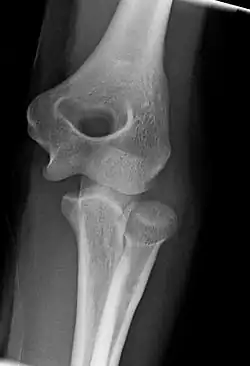

The elbow undergoes dynamic development of ossification centers through infancy and adolescence, with the order of both the appearance and fusion of the apophyseal growth centers being crucial in assessment of the pediatric elbow on radiograph, in order to distinguish a traumatic fracture or apophyseal separation from normal development. The order of appearance can be understood by the mnemonic CRITOE, referring to the capitellum, radial head, internal epicondyle, trochlea, olecranon, and external epicondyle at ages 1, 3, 5, 7, 9 and 11 years. These apophyseal centers then fuse during adolescence, with the internal epicondyle and olecranon fusing last. The ages of fusion are more variable than ossification, but normally occur at 13, 15, 17, 13, 16 and 13 years, respectively.[16] In addition, the presence of a joint effusion can be inferenced by the presence of the fat pad sign, a structure that is normally physiologically present, but pathologic when elevated by fluid, and always pathologic when posterior.[17]

Fractures

There are three bones at the elbow joint, and any combination of these bones may be involved in a fracture of the elbow. Patients who are able to fully extend their arm at the elbow are unlikely to have a fracture (98% certainty) and an X-ray is not required as long as an olecranon fracture is ruled out.[27] Acute fractures may not be easily visible on X-ray.[28]